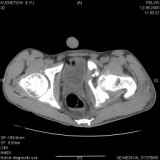

Уважаемые коллеги! Хотелось бы услышать совет по тактике лечения представлленого больного.Поступил после лечения в одном изотделений области. Травма 2,5 месяца назад. После выведенияиз шока был произведен остеосинтез перелома бедра, предплечья, до перевода к нам проводилосьвытяжение по оси шейки бедра за стержень, введенный в большой вертел. На сегодня деформацияригидна, клинически мобильности не определяется. Заранее признателен. P.S. Данный вид травм не включен в перечень "высокотехнологичных операций", направить длялечения по квотам Минздрава очень сложно.

Это обзорные и косые снимки

Привет, Леонид. Оскольчатый высокий двухколонный перелом в такие сроки трогать не надо, т.к. это про такие переломы сказано: "кто с ножом на Ж. пойдет тот в ней и останется...".

Тяжелый случай... Поздняя реконструкция такого перелома технически сложное дело, вероятность осложнений,неуд.результатов выше(на PubMed article Johnson, Mast, Matta, Letournell results of acetabular reconstruction 20-120 days after injury).

Принимая во внимание обширность реконструкции, вероятность осложнений( остеоартроз, аваскулярный некроз), которые в любом случае должны будут решаться артропластикой сустава, пожалуй, я бы не стал оперировать сейчас: складывать мозаику многооскольчатого перелома, мобилизуя фактически сросшиеяся воедино фрагменты - дело травматичное с сомнительным результатом.